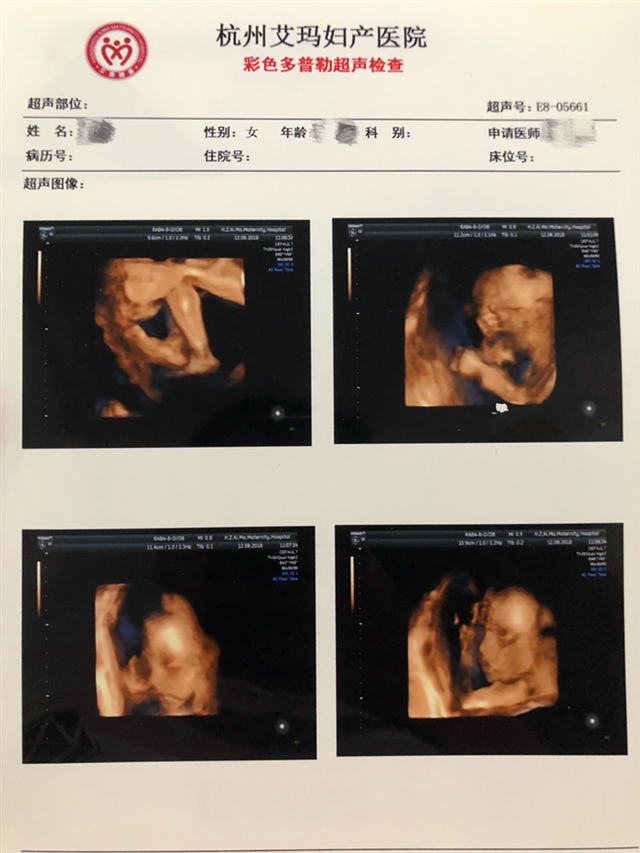

孕20周+0天